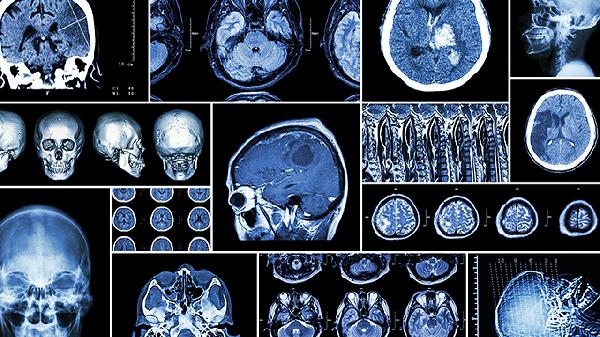

使用利伐沙班片期间可能出现牙龈出血、鼻出血等轻微出血症状,严重时可发生消化道出血或颅内出血。肾功能不全患者需调整剂量,同时避免与其他抗凝药物联用。